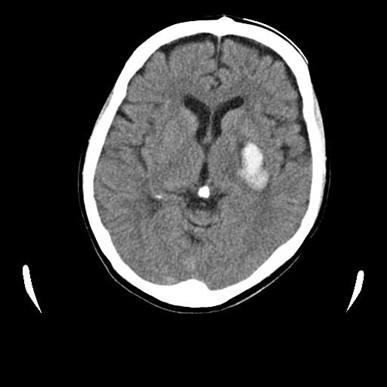

A 57-year-old woman developed a hemorrhage of approximately 30×18 mm in the left capsular region (lenticulostriate artery), and pain and numbness in the right half of the body at age 53years (Figure 1). The modified Rankin Scale (mRS) was 4. The patient was able to walk, but due to pain, numbness and allodynia, she had a spastic gait and difficulty lifting her legs. She suffered frequent pain and numbness in the upper limbs, even at rest. She had no muscle weakness in the upper and lower limbs, and could maintain motor function in daily life; however, she had complaints of slow gait, numbness, pain and decreased sensation.

Figure 1 Head CT findings: Left capsular hemorrhage.